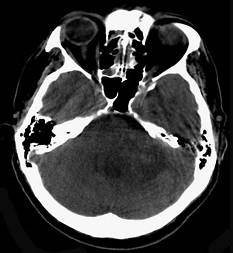

问题 有关听神经鞘瘤(如图所示)的发生,下列哪项描述不正确()

选项 A.多发生于听神经的内听道段或内耳孔区 B.听神经瘤起源于Schwann细胞 C.听神经瘤多来自耳蜗神经 D.大多数是单侧性 E.好发于中年人

答案 C